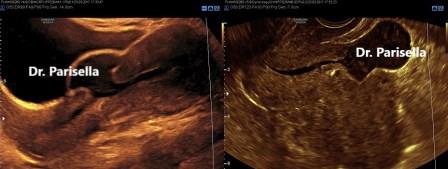

Nell'immagine sottostante si evidenzia una rottura d'utero fuori gravidanza: a sinistra con approccio sovrapubico, grazie al contrasto della vescica, l'immagine è facilmente interpretabile; a destra con sonda transvaginale l'immagine è meno suggestiva.